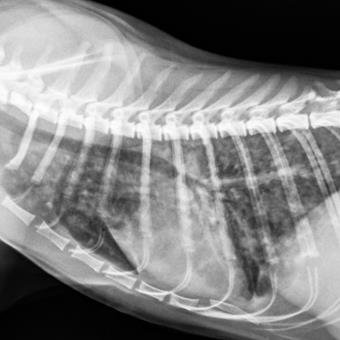

Aérostrongylose chez le chat

L’aélurostrongylose, bien que rare, est la maladie parasitaire respiratoire la plus fréquente chez le chat.

Les vers adultes font 5 à 10 mm et vivent dans les petites voies respiratoires où ils pondent des œufs. Les œufs éclosent en larves qui migrent vers l’intestin et sont éliminées dans les selles.

La détection de larves dans le lavage bronchoalvéolaire ou dans les selles par coproscopie permet de confirmer le diagnostic. Le traitement repose sur l’utilisation de certains antiparasitaires.